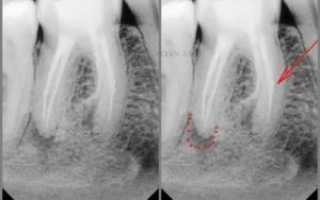

Итак, в этом случае мы видим на снимке «спиральку» в одном из каналов… Она показана стрелкой. Точками обведен воспалительный очаг вокруг корня зуба.

Чтобы хорошо очистить корневые каналы, стояла задача удалить этот отломок. При этом он находился довольно глубоко и имел небольшие размеры. Без вооруженного микроскопом глаза задача была бы трудновыполнимой. На фото ниже красной стрелкой показан отломок в глубине канала. Видя его, стоматологу уже намного легче обломок убрать и вывести наружу (зеленая стрелка).